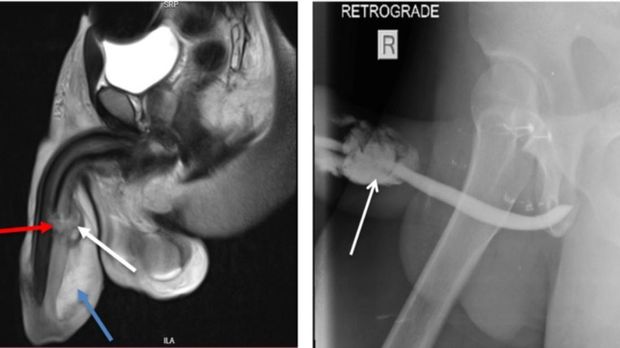

penis patah Foto: Sciencedirrect |

Pemeriksaan MRI atau Magnetic Resonance Imaging menunjukkan adanya robekan dari kiri ke kanan melalui tunica albuginea, corpora carvenosa, dan corpus spongiosum, yang merupakan jaringan ereksi. Pemindaian juga menunjukkan bahwa ada robekan sebagian melalui uretra dan pembengkakan. Meski tidak ada tulang di penis, luka ini masih dikenal sebagai 'fraktur' penis.